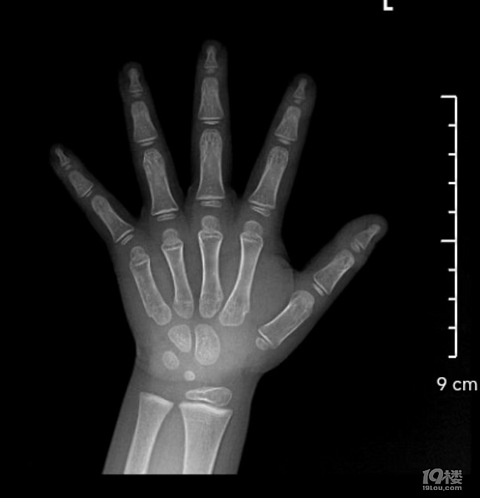

男娃身材一直偏矮,目前11岁5个月,身高143cm,骨领12.6了,偏大一岁多;体重86斤,拍了b超,身体已经快速在发育了,医生说按照这个快速发育的节奏,身高也应该快速增高,但并没有明显增高现象,预测身高160左右,男娃。医生给出了可以药物干预,也就是打生长针吧,有没有什么副作用?